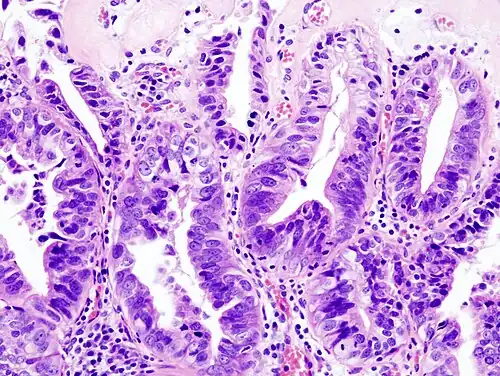

-

Gallbladder adenocarcinoma lymphatic invasion histopathology -

Incidentally discovered gallbladder cancer (adenocarcinoma) following a cholecystectomy. -

Gallbladder adenocarcinoma histopathology